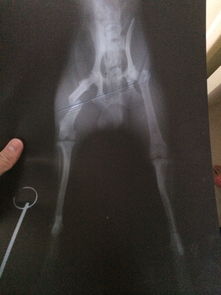

看了你追加描述和圖片,基本確定是骨折!不打算去醫院的話(huà)就按照我上面說(shuō)的做,狠狠心找到骨折的地方,試著(zhù)做一下整復,外邊用硬紙殼固定!可以去買(mǎi)一些人藥!狗狗會(huì )很快好起來(lái)的

哎。我家就是。大年三十那天自己從沙發(fā)跳下來(lái)以后,前腿一只就不粘地了,嗷嗷嗷的叫了半天。剛開(kāi)始走路都不會(huì )了。三條腿不習慣,正好趕上過(guò)年,寵物醫院什么的也不方便.我摸了摸骨頭,沒(méi)什么異常..也沒(méi)固定,以為第2天能好,結果第2天只3條腿走路??蛇^(guò)年沒(méi)人啊。等3天左右吧,發(fā)現前腿直的那條骨頭居然像V字一樣突起了..我期間一直喂的紅藥。.

給醫院打電話(huà),說(shuō)內固定3000。外固定700左右。有點(diǎn)貴。家人不同意我治。狗花4000買(mǎi)的- -!說(shuō)不想再花錢(qián)勒。..我只好自己給做了個(gè)外固定,用雪糕棍什么的。..

到現在,1個(gè)多月過(guò)去了。.跑跳都可以了.就是那腿,還是沒(méi)直。..看樣子也是直不了啦。.我就一直外固定呢。.還好沒(méi)影響到它什么。長(cháng)短腿了。..

你如果有條件,最好帶醫生那里,把骨頭位置掰正!讓受傷部位對齊.然后自己做外固定長(cháng)好!我家就沒(méi)對齊,直接外固定了,,,,哎。沒(méi)辦法。.